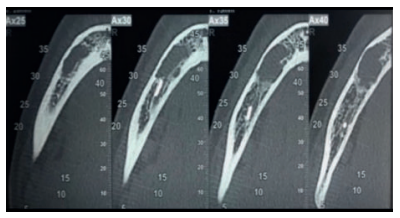

Se solicitó como prueba complementaria un CBCT mandibular. En los cortes panorámico, axiales y ortorradiales, se corroboró la presencia de lesión radiotransparente delimitada de contorno algo irregular y que no provocaba expansión de corticales (Figuras 1-4).

Radiográficamente presenta una imagen radiotransparente unilocular mostrando un festón en el área interradicular de los dientes afectos y de zonas edéntulas, pudiendo incluir sus raíces en la lesión, pero sin rizolisis; aunque en el sector anterior acostumbra a tener forma ovalada. Es radiotransparente con bordes irregulares, pero bien definidos. La expansión ósea sin perforación de corticales serían criterios asociados a esta lesión benigna, erosionando el endostio y por tanto adelgazando la cortical 2,3,5,6 .